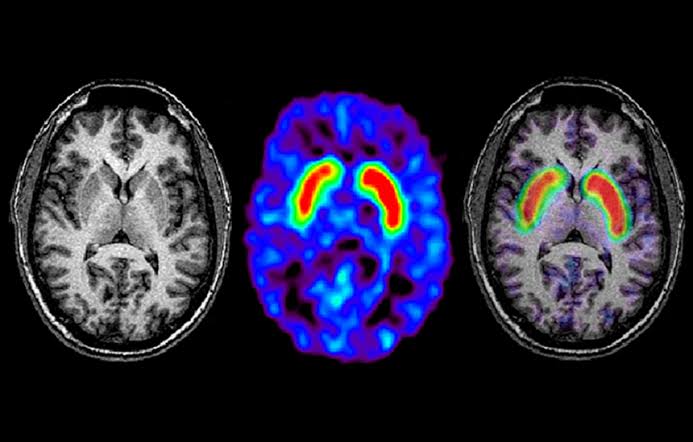

The cause of Alzheimer disease is unknown. Scientists know that in Alzheimer disease there is large build-up of proteins called amyloid within brain cells. These proteins occur normally, but not yet understand why they build up in large amounts. The disease process can go on for many years without symptoms, but as more and more proteins form brain cells,the cells lose their ability to function and eventually die. This causes the affected parts of the brain to shrink.

- Drugs used to block the production of Beta-amyloid proteins are under development also attempts are under way to develop vaccines that would allow the body’s immune system to produce antibodies to attack these proteins.